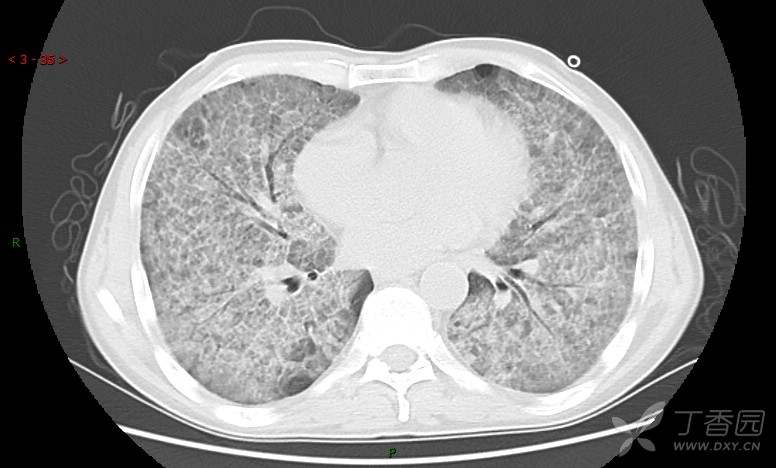

地图+铺路石征=PAP?那升高的CEA怎么说(病例3连发,附其他2例链接)

患者男,42岁,咳嗽半年余,加重伴憋喘2月余。

患者半年余前无明显诱因出现间断咳嗽,干咳为主,偶咳少量黄白痰,剧烈咳嗽或运动后可出现轻度憋喘,无高热、脓臭痰,无胸痛、咯血及晕厥,无低热乏力及盗汗,无心前区压榨感及夜间阵发性呼吸困难,初未在意,未予正规诊治。2月余前患者自觉上述症状较前加重,咳嗽、憋喘明显,黄白色粘痰略有增多,伴有发热,热前伴有畏寒、寒战,体温最高达38.9℃,先后就诊多家医院,入住重症监护室,未行气管插管,考虑“重症肺炎”,给予“美罗培南、复方磺胺甲噁唑”等药物抗感染,“卡泊芬净”抗真菌,并给予“甲泼尼龙”等药物治疗35天,经治疗后症状好转于2018-04-02出院。患者自出院后仅应用中药治疗(具体不详),并给予家庭氧疗,平素仍有间断咳嗽,咳少量黄白色粘痰,活动后憋喘明显,活动耐量差,以卧床为主。